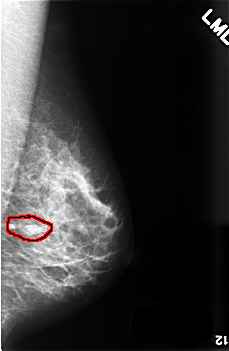

FILE: C_0507_1.LEFT_MLO.OVERLAY

TOTAL_ABNORMALITIES 1

ABNORMALITY 1

LESION_TYPE MASS SHAPE OVAL MARGINS CIRCUMSCRIBED

ASSESSMENT 3

SUBTLETY 5

PATHOLOGY BENIGN

TOTAL_OUTLINES 1

BOUNDARY